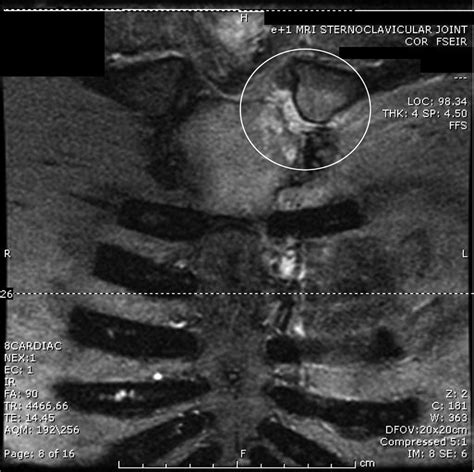

Diagnostic procedures for sternal costal joint issues may include:

• Physical Examination: A healthcare professional will examine the chest area for tenderness, swelling, and any signs of injury. They may also assess the range of motion and any pain during movement.

• Medical History: The patient's medical history, including any recent injuries or illnesses, will be reviewed to identify potential causes of the symptoms.

• Imaging Tests: X-rays, CT scans, or MRI scans may be used to visualize the sternal costal joints and surrounding structures. These tests can help identify fractures, inflammation, or other abnormalities.